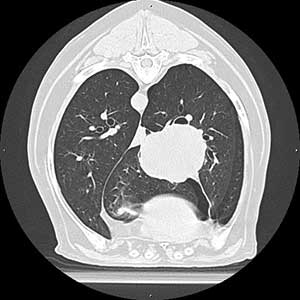

Wir sind zwei unabhängige Veterinärradiologinnen, die Ihnen gerne zur Seite stehen, wenn es um die Beurteilung und Durchführung von Bildgebenden Untersuchungen bei Hunden und Katzen, aber auch Heimtieren, Vögeln und Exoten geht. Wir beurteilen Röntgen-, CT- und MRT-Bilder und führen Ultraschalluntersuchungen durch.